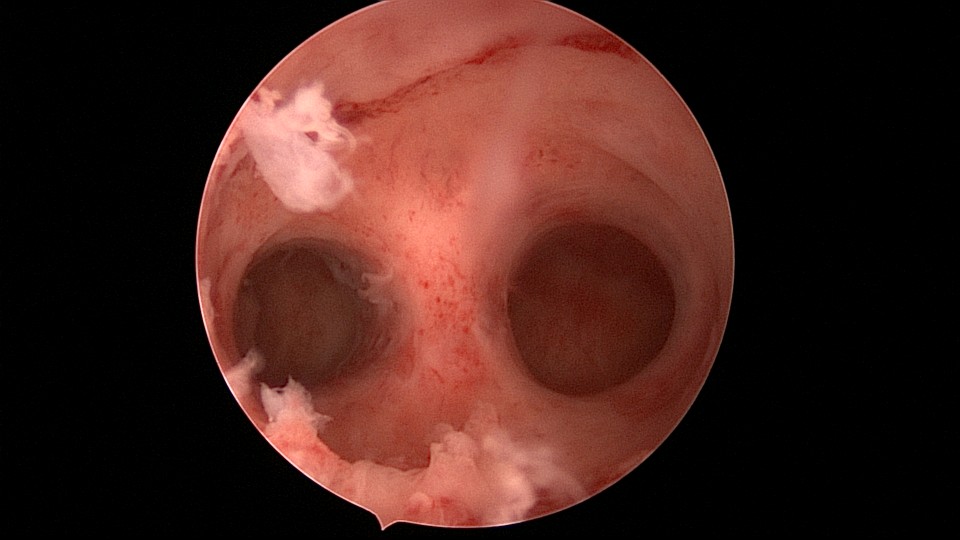

患者29岁,G1P0,继发不孕,2020年8月宫腹腔镜探查,大网膜与腹前壁多处粘连,子宫后壁与直肠前壁广泛粘连,宫腔中央型宽大柱状粘连,宫腔两侧少许粘连。电钩分离盆腔粘连,冷刀分离宫腔粘连,恢复宫腔形态,显露双侧输卵管开口,术中美兰通夜,双侧输卵管通畅。2020年10月宫腔镜二探取球囊,宫腔形态正常,双侧输卵管开口可见。2021年3月自然妊娠,外院足月分娩。现34岁,G2P1。